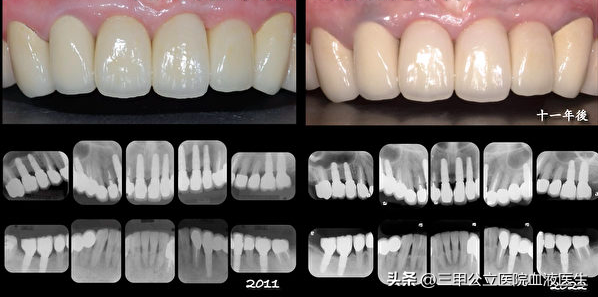

成功的種植牙有舒適美觀、穩(wěn)固牢靠、持久三大優(yōu)勢,能修復恒牙缺失,重建咀嚼功能,提高人類生存質(zhì)量,因此種植牙被譽為“人類的第三副牙齒”